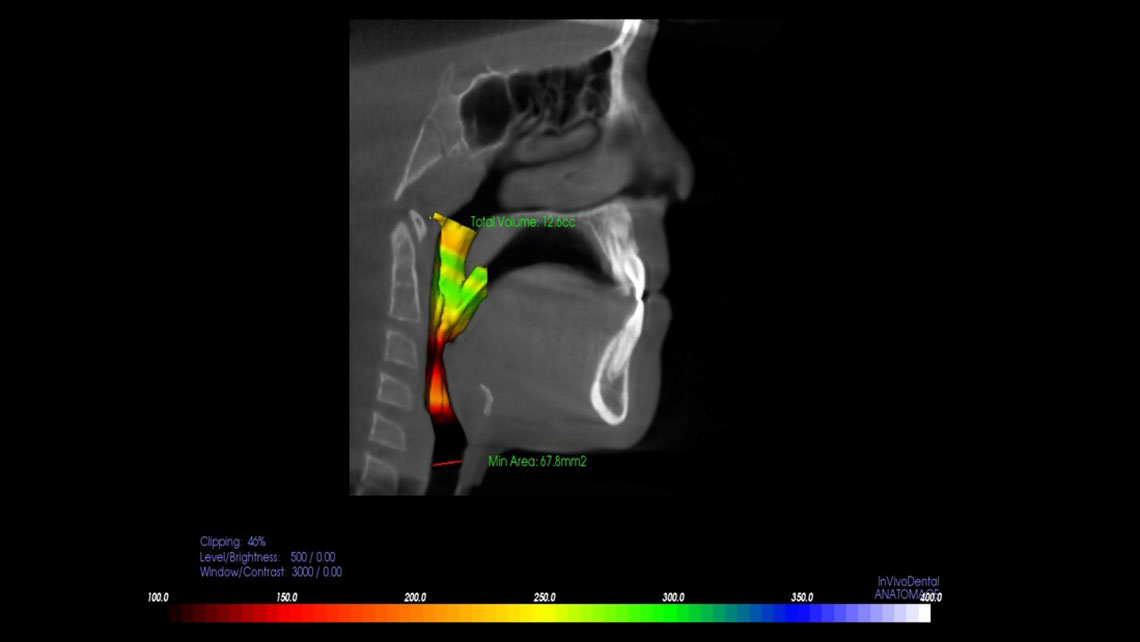

TMJ, Sleep Therapy & Airway Orthodontics utilizes the most advanced technology available. Our i-CAT® FLX Cone Beam 3D system is designed to provide greater flexibility in scanning, planning, and treatment. This latest advancement of our award-winning technology offers a range of innovative features that deliver increased clarity, ease-of-use, and control.

The i-CAT® FLX offers the most flexible imaging control of any cone beam 3D unit, allowing Dr. Walker to target the desired field-of-view on each patient while minimizing the dose. With i-CAT® FLX, Dr. Walker can customize scanning options for greater control of the field-of-view, dose and resolution for a perfect image.